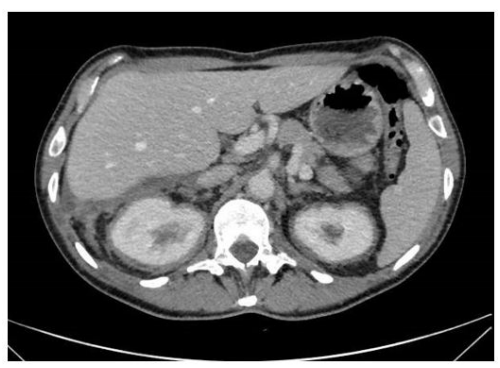

Chest X-ray showed interstitial thickening of lung, ilo-perilary congestion and bilateral pleural effusion major on the left. The findings were investigated with contrast enhanced CT of chest and abdomen, which documented the presence of solid tissue infiltrating both pleurae, mediastinal fatty tissue and pericardium, perirenal fascia and perihepatic area, and surrounding the aortic arch, the proximal tract of the epiaortic vessels.

The clinical presentation is variable as it may range from an indolent focal disease to a life threatening organ failure. [4] ECD may virtually affect any organ system. Ihe most frequently involved site is the skeleton (96% Of ECD patients), Often associated With bone pain. A pathognomonic finding is bilateral cortical sclerosis involving the diametaphyseal regions, typically observed on radiographs, associated with an abnormally strong labeling on 990iTc bone scintigraphy. Cardiovascular involvement IS frequent too (75% of cases), mostly presenting as pericardial infiltration, periaortic sheathing ("coated aorta") and myocardial infiltration [51, Central nervous system involvement appears in 51 % of ECD cases, with central diabetes insipidus being the most common finding Pulmonary involvement (43% Of cases) can lead to an interstitial lung disease or pleural effusion. ECD associated involvement of the retroperitoneal space is reported in 68% of the patients, most of which asymptomatic, and infiltration of the perirenal fat produces a typical "hairy kidneys" appearance on CT scan images [7].

In fact, the imaging examinations performed during the last hospitalization showed a multiorgan involvement, in. duding coated aorta, hairy kidney. long bone thickening lesions, that lead us to consider a systemic disease. All that findings were consistent with the diagnosis of ECD, which was further corrob- orated by the histological finding of foamy histiocytes containing lipids reactive for CD68.